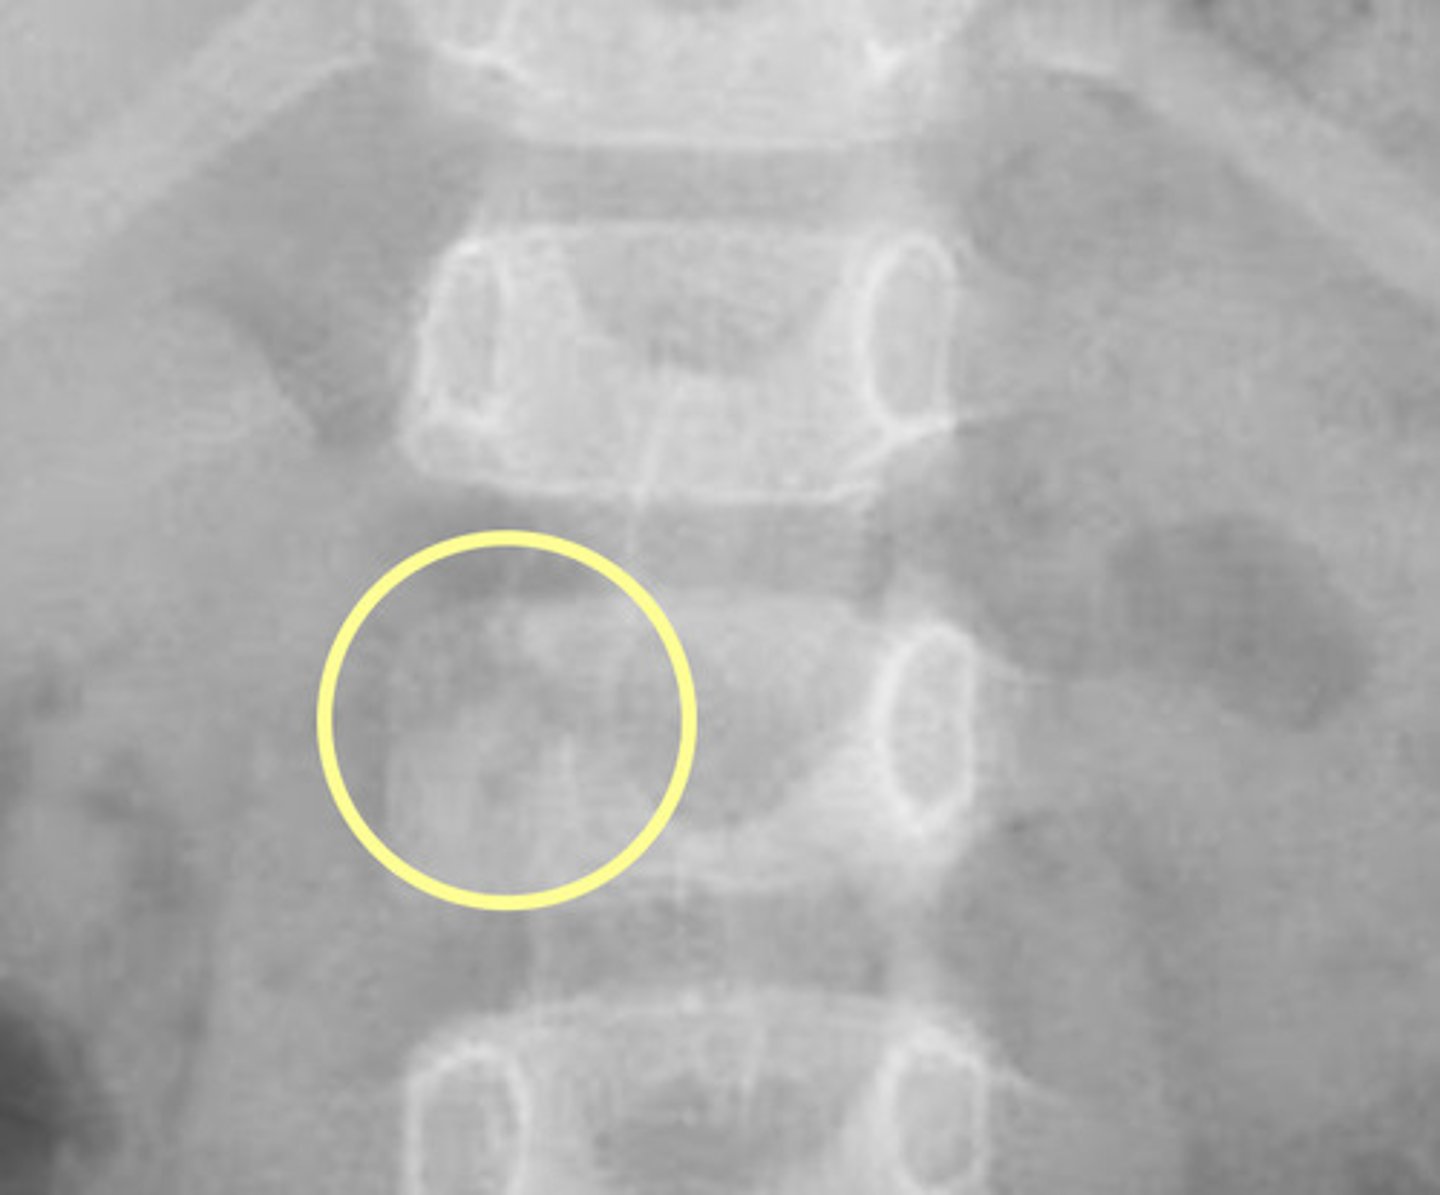

Image example of sacralization of L5